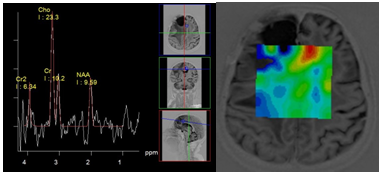

Some authors argue that chronic foci in various forms of MS can show differences in metabolite profiles. Thus, in relapsing forms, an increase of myo-inositol (M-Ins/Cr) and a significant reduction in N-acetylaspartate (NAA/Cr) can be observed, in contrast to the benign form of disease (Figure 1).5

Figure 1 Multiple sclerosis, PRESS, TE 30 ms spectrum of metabolites of chronic plaque (a) and normal looking white matter (b). High concentration of myo-inositol is suggestive of relapsing-remitting form of disease.